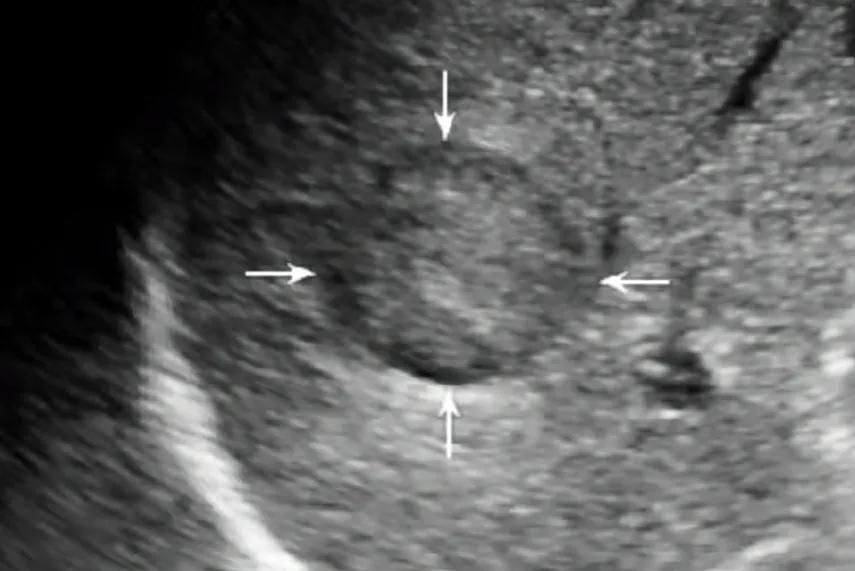

肝囊肿的诊断通常较简单, 普通的超声即可确诊 ,直径5mm左右即可被超声显示,典型的超声表现是,肝脏上显示的圆形或椭圆形无回声区 。

超声所见:直径<3cm的肝癌结节常常包膜完整,癌结节内部回声高低不一,且具多变倾向,癌结节可有低回声结节、高回声结节、混合性结节,还可以是等回声结节。肝癌结节及其周围血供丰富,彩色多普勒超声能准确反映肝癌的血供情况。

肝癌超声声像图